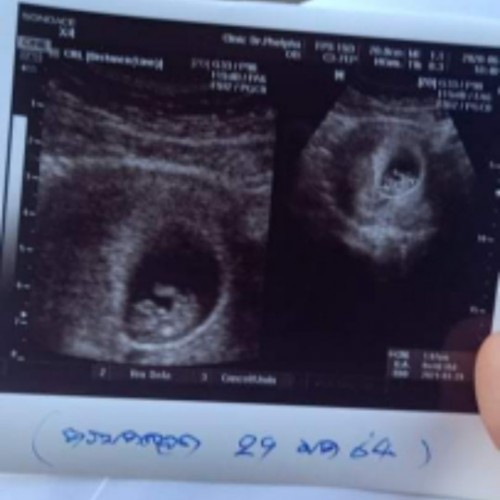

คลอด 29 มกราคมจ้า 16w